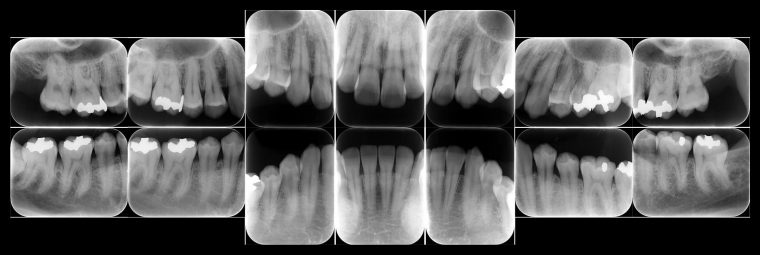

症例5

before

症例

after

歯周病検査(治療前)

歯周病検査(治療後)

レントゲン写真

基本情報

年齢・性別 32歳・男性

主訴 主訴:歯ぐきから出血する

治療部位:全顎

治療内容 「全顎」

歯周基本治療(歯周精密検査、スケーリング、OHI、SRP)

治療期間 約3ヶ月

治療費 歯周基本検査:約600円(保険診療3割負担)

スケーリング、OHI:約2,000円(保険診療3割負担)×2回

SRP、OHI:約1,500円(保険診療3割負担)×4回

歯周精密検査:約1,200円(保険診療3割負担)×2回

合計金額13,000円

(2025年2月現在)

リスク・副作用 歯石を取った後に、歯がしみることがあります。

治療方針 ①検査

レントゲン、口腔内写真を撮影して、歯や歯周組織の状態を確認します。

また、歯周病の検査で歯周ポケットの深さや出血の有無を確認します。

②スケーリング、OHI(口腔衛生指導)

スケーリングをして歯の表面の歯石を除去します。

また、正しい歯磨きの仕方や、フロスの通し方を一緒に確認します。

③歯周精密検査

前回歯石除去と歯磨き指導を行なった結果、歯ぐきの状態がどれぐらい改善したか検査します。

④SRP

歯ぐきの内側についてる歯石を除去します。

⑤歯周精密検査

SRP後、歯周病が改善されたか、検査します。

歯周ポケットが4ミリ以上の部位は、再度SRPを行います。

今回は歯周病の状態が安定したため、3ヶ月おきの定期検診で歯周病の再発や進行を防ぎます。

特記事項 歯周精密検査について:

・歯周ポケットが4ミリ以上ある場合は歯周病で、3ミリ以下は健康な歯ぐきです。

・出血の有無で炎症があるか確認します。

・磨き残しがある部分を確認して記録します。

担当者所見 初診時は、写真を見て分かるように、歯ぐきが赤く腫れていました。

また、歯周病の検査では、全体的に歯と歯の間の部分の歯周ポケットが4ミリあり、全体の約81%から出血が認められました。

出血量も多く、歯ぐきに触れた瞬間に出血しました。

レントゲンで骨のレベルがしっかりとあることが確認できました。

そのため、ご自身で正しい歯磨きを継続することで改善すると考えました。

歯周基本治療を経て、再度検査した結果、歯周ポケットはほぼ3ミリ以下に改善しました。左下7番の残存した歯周ポケットは、隣の親知らずを抜いたため経過観察します。

出血率は約4%まで改善し、出血量も点状で少なくなりました。

今後は右上2番、右下3番の歯ぐきの発赤の改善と、出血率0%を目指して、定期検診でメンテナンスしていきます。